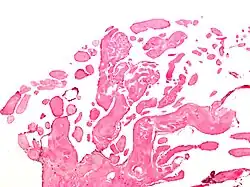

| Low magnification micrograph of an excised aortic valve papillary fibroelastoma showing the characteristic avascular branching papillae, H&E stain | |

Papillary fibroelastoma are typically found and accurately diagnosed by imaging. The diagnosis is confirmed by pathology. Histologically, papillary fibroelastomas have branching avascular papillae, composed of collagen, that are covered by endothelium.